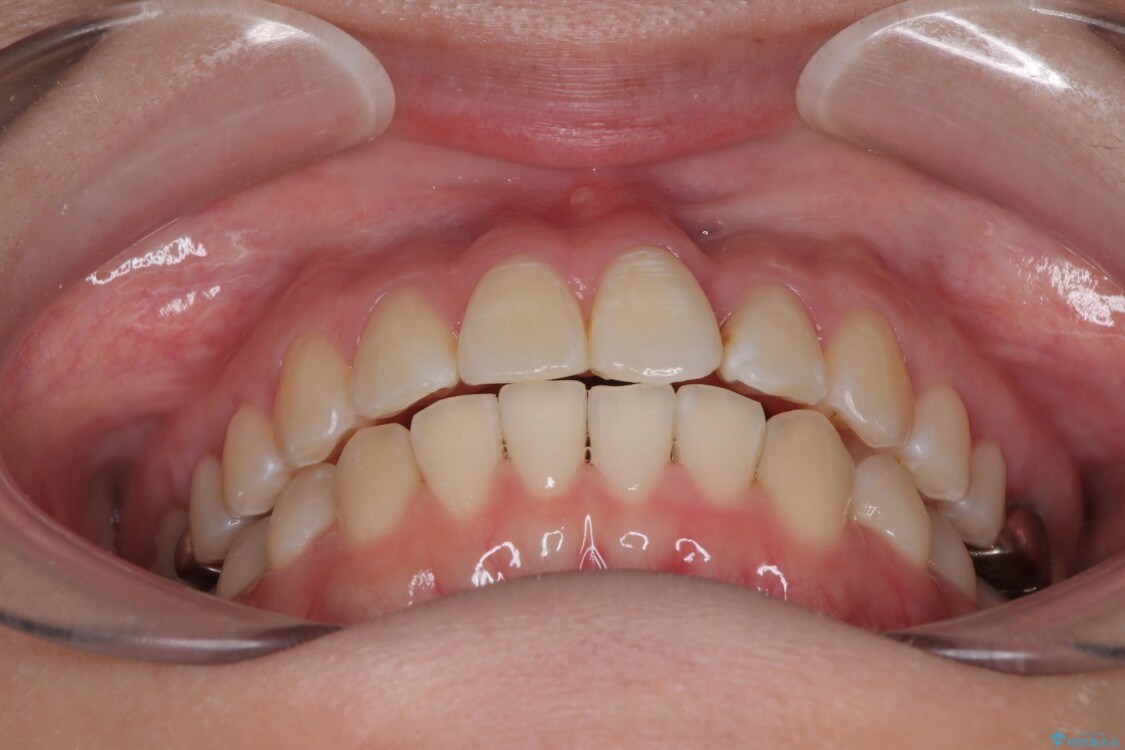

治療後

• 前歯のねじれ・ガタガタを10か月で改善!20代女性の矯正治療|クリアブラケットでむし歯になりにくい歯並びへ改善 治療後画像

矯正治療期間はわずか10か月と、比較的短期間で終了しました。

前歯のデコボコがなくなり、見た目の印象が大きく変わっただけでなく、歯磨きがしやすくなり、むし歯や歯周病のリスクが大きく減少しました。